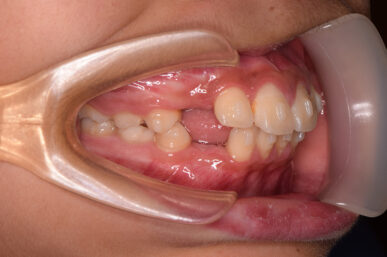

• Before

治療開始が遅くてこのままでは犬歯の生えるスペースが不足していて八重歯になるところでしたが、アライナー矯正で素早く歯を動かして犬歯が生えてくるスペースを作ることで八重歯にならずに済みました。

八重歯のケースは永久歯の抜歯が必要になることもありますが、避けることができました。